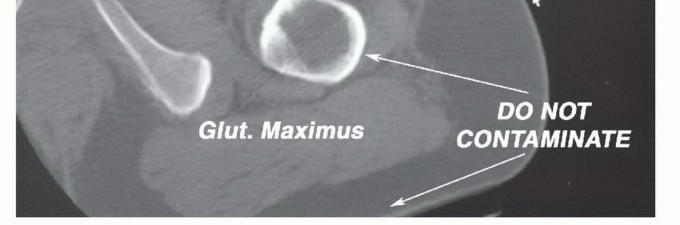

Biopsy Principles

The biopsy tract must be considered contaminated and must be excised en bloc with the tumor. For posterior flap hemipelvectomies, the biopsy must be placed anteriorly or laterally, strictly avoiding the posterior gluteal tissues. The operating orthopedic oncologist must dictate the biopsy trajectory.

Contamination of Surrounding Structures

Inappropriate, poorly planned biopsies or unplanned intralesional excisions ("whoops" procedures) can contaminate multiple anatomic compartments. Similarly, pathologic fractures of the proximal femur with massive hematoma tracking can contaminate vast tissue volumes, precluding safe limb salvage and necessitating amputation.